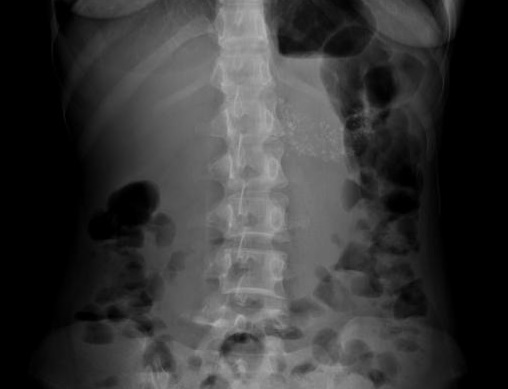

A gauche de L1 on peut en voyait image

des petites nodules et des taches calcifies du

pancreas .Image radiologique ASP de face de

l'abdomen d,une pancreatite chronique . Image

de calcification du pancreas en ce cas est tres

nette |